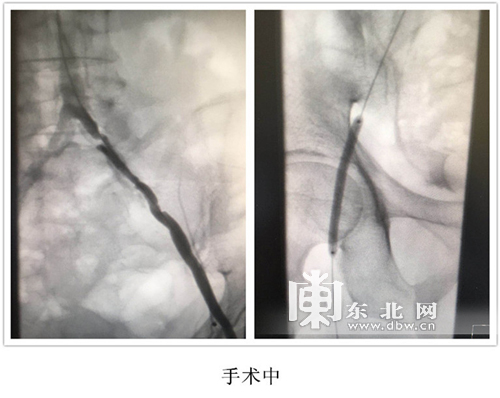

患者入院后,董军医生首先对患者的身体情况进行了重新评估。患者入院时血压180/100mmHg,心功能不达标,经一周调整,血压平稳心功能达标可以进行手术。然而术中造影时,患者双髂动脉重度狭窄,近乎闭塞,如按传统介入治疗方法,需二次手术分别开通双髂动脉,董军医生果断决定采取目前先进的渐进式介入治疗,即借助导丝先扩张狭窄闭塞的患侧髂动脉,待患侧髂动脉改善后,再行健侧治疗。这在哈尔滨市第四医院尚属首例,由于髂动脉自身结构和位置的特殊性,手术难度相对较大。在患者的积极配合、导管室医护人员的通力协作下,董军医生、于林峰医生成功完成双髂动脉球囊扩张支架置入术,为患者一次解决双髂动脉闭塞,节省医疗费用近万元。术后患者恢复良好,满意度高,生活质量得到很大改善。